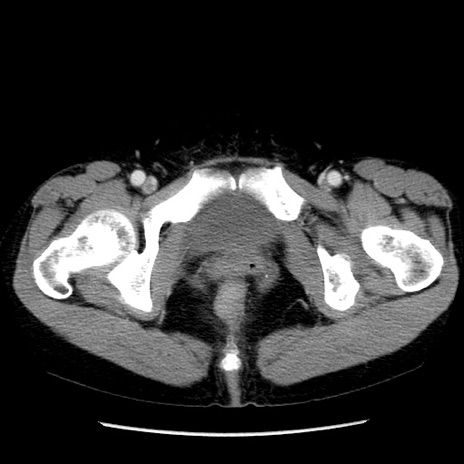

症例6(横断像)

【症例】50歳代女性

【主訴】下腹部痛

【現病歴】本日朝より下痢2回あり。 昼食を食べた後、嘔吐3回、下腹部痛認め、症状軽快せず、当院救急搬送。

最終食事:本日昼(生ものなし)。 昨日の夜、刺身を食ぺたとのこと。周囲に同様の症状の者なし。普段、排便は毎日あるとのこと。

【既往歴】卵巣癌術後(8年前に当院で卵巣摘出)

【身体所見】 意識清明、腹部:平坦、腸蠕動音→、やや硬、下腹部自発痛・圧痛あり、反跳痛あり、筋性防御なし。

【データ】WBC 16000、CRP 0.01